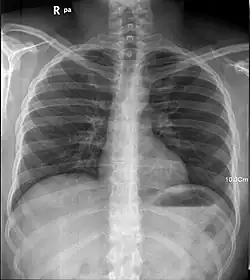

Rayon X des poumons humains

Rayon X sur poumons humains.